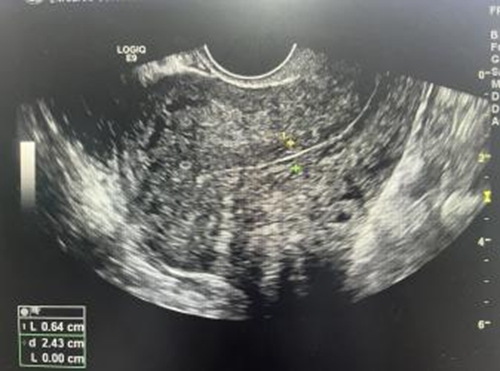

術后半個月,胎盤組織就自行排除,超聲提示植入的胎盤病灶明顯縮小。術后1個月再次復查超聲,胎盤已自行排除干凈,宮腔內沒有異常回聲。

#術前病灶范圍較大 >>

#術后1個月恢復正常宮腔形態(tài) >>